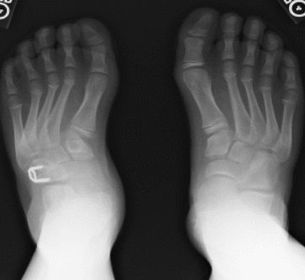

What deformity is this? | Metatarsus Adductus |

What deformity is this? | Skew foot |